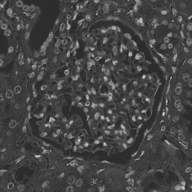

Image datasets in digital pathology applications often consist of consecutive slides stained differently, each staining providing specific information on the same region of interest (see Figure 1, first row). Even though differently stained slides appear very different, there is often a significant amount of consistent information between them. For example, they may both share the same counterstain (e.g. haematoxylin), or they may highlight different parts of the same structure.

Objects to be segmented, e.g. glomeruli, are generally easily identified between stainings as globally they exhibit the same structure and texture, see Figure 1. It should therefore be possible to bias the network to learn stain invariant features. This work investigates this possibility by modifying the data presented to the network in an unsupervised manner. Borrowing domain adaptation terminology, herein the staining used for training and validation is referred to as as the source staining (irrespective of any transformations), and the stainings to which the network are applied as target stainings.

The last strategy, named Colour Transfer, restricts this to within meaningful bounds at the expense of being more complicated. The colour profile of each training patch is replaced with that of a randomly selected staining during training with probability , where is the number of stainings in the dataset. Therefore each ‘staining’ (including the source) is presented to the network with equal probability. The colour transfer is achieved by deconvolving the patch and applying its stain concentrations to stain vectors taken from another staining. Various approaches to this exist [16, 17, 18] (including computer vision approaches [19]), in this work we use that proposed by Macenko et al. due to its simplicity (automatic determination of stain vectors) and realistic output (see Figure 1, bottom row). It is necessary, however, to have samples of the target stainings to determine their stain vectors (this requirement can be removed by using predetermined stain vectors and Ruifrok and Johnston’s approach [15]). During training, a random patch from a random target staining is selected and the target stain vectors are determined.

N.B. the intention is to present plausible colour profiles to the network. This does not necessarily correspond to biologically relevant image information but is explored for any potential for the tested staining modalities. Potential limitations are addressed, e.g. in Figure 1 the bright red colour (chromogenic reaction used to detect CD34, a marker of blood vessel inner lining) could be successfully transferred but it is not localised as in the original image.

Finally, colour variance is restricted to a more realistic range using colour transfer, giving the best results in all cases. It should be noted that the quality of the result is highly dependent on the degree of structural similarity between the target and source staining. Visually, there is a large difference between histochemical staining methods (e.g. H&E, PAS, Jones) and immunohistochemistry (antibody-mediated detection of certain structures like immune cells of blood vessel inner lining) with weak blue counterstain. Therefore, some limitations of the approach are expected, and the degree of variation may explain why detection of glomeruli in the CD68 staining did not work well with PAS as source staining.